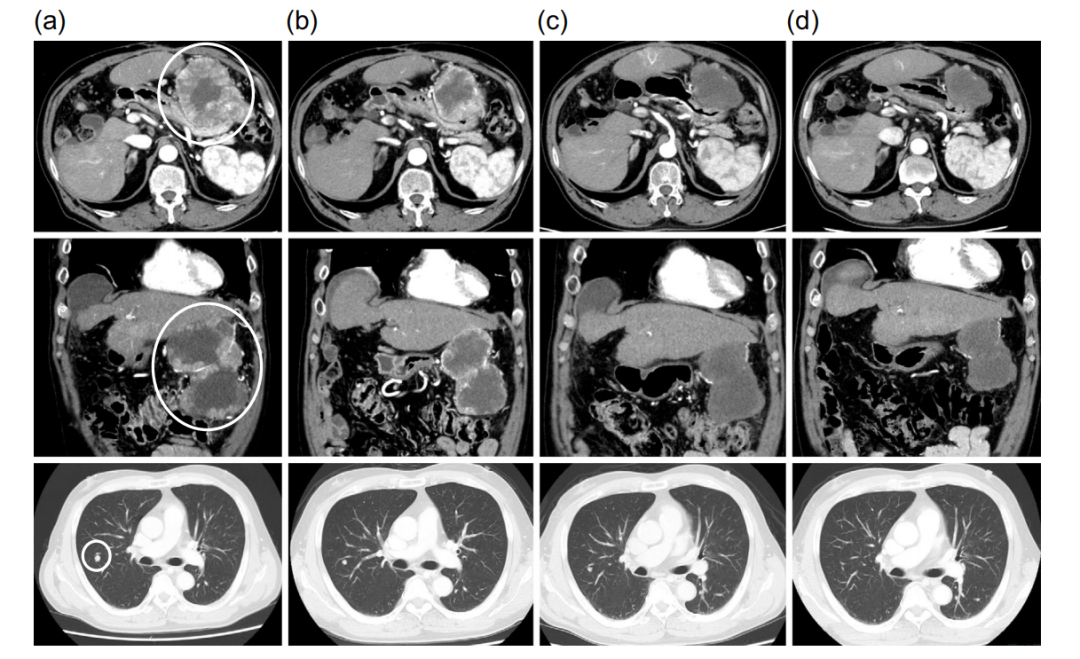

既往手术史

患者因HCC破裂接受了急诊经导管动脉栓塞术(TAE),随后接受了肝第5段部分切除术和肝第6段亚段切除术。肝切除术后6个月,患者因腹膜播散再次在附近医院接受TAE,并行大网膜结节切除术和部分降结肠切除术。第二次手术7个月后,CT显示肝第7节段HCC复发并伴有腹膜播散。经导管动脉化疗栓塞(TACE)治疗肝7段。TACE术后1个月CT显示肝内肝癌复发及肺转移。

一线索拉非尼耐药

患者开始服用800mg/天的索拉非尼(标准剂量),没有出现不良事件。但治疗3个月后病情进展(PD),索拉非尼被判定无效。

瑞戈非尼二线治疗实现降期转化

瑞戈非尼的起始剂量为160mg,每天口服一次,用3周停1周。治疗初期,患者出现3级低磷血症,对症治疗后得到了改善。开始瑞戈非尼治疗 9个月后,由于出现2级手足综合征,暂停使用瑞戈非尼。停用10天后,他重新服用瑞戈非尼,剂量降低为标准剂量的一半,即80mg,每天1次。减少剂量后,没有出现不良事件,所以在减少剂量9个月后,瑞戈非尼的剂量增加到160mg/天。患者在接受瑞戈非尼治疗10个月时病灶就达到部分缓解(PR)。

AFP水平从最大值47,050 ng/mL下降到24.6 ng/mL,DCP水平从最大值56171 mAU/mL下降到38 mAU/mL。